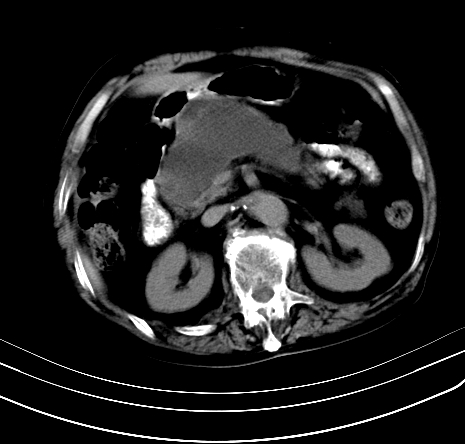

上腹部疼痛不适,行ct检查

胰腺明显肿大,密度减低,考虑慢性胰腺炎,假性囊肿形成不除外。

胰腺较明显扩大,胰周有渗出;肾周筋膜有增厚渗出,以左肾为著。应考虑急性胰腺炎。

慢性胰腺炎,假囊肿形成,脂肪肝。